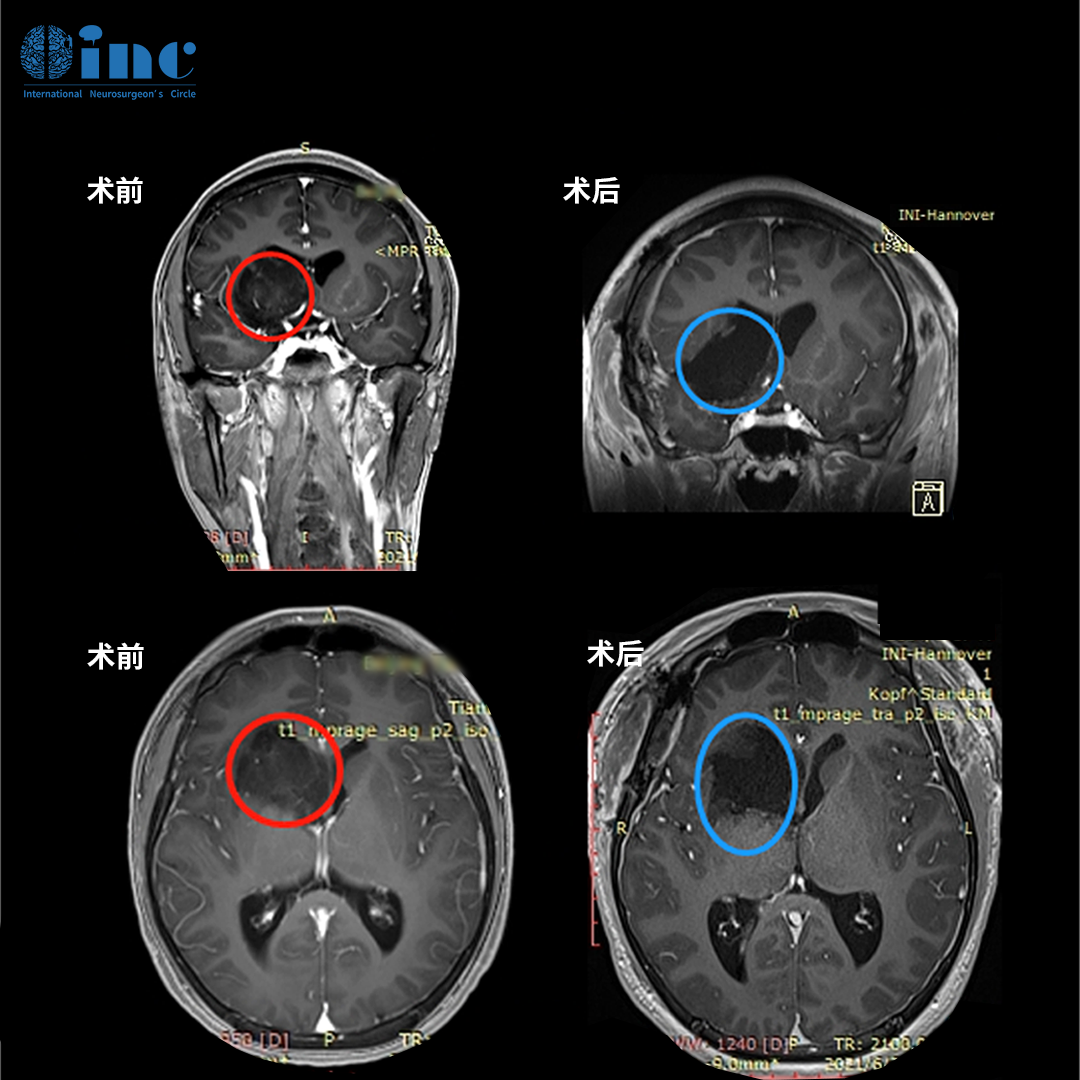

基底節(jié)膠質(zhì)瘤案例

圖:術(shù)前術(shù)后MR磁共振對(duì)比,術(shù)前丘腦較大占位,壓迫島葉及腦室,腦室增大。術(shù)后MR提示腫瘤大概率以上全切,近全切,占位效應(yīng)解除,無(wú)新發(fā)腦損傷等。